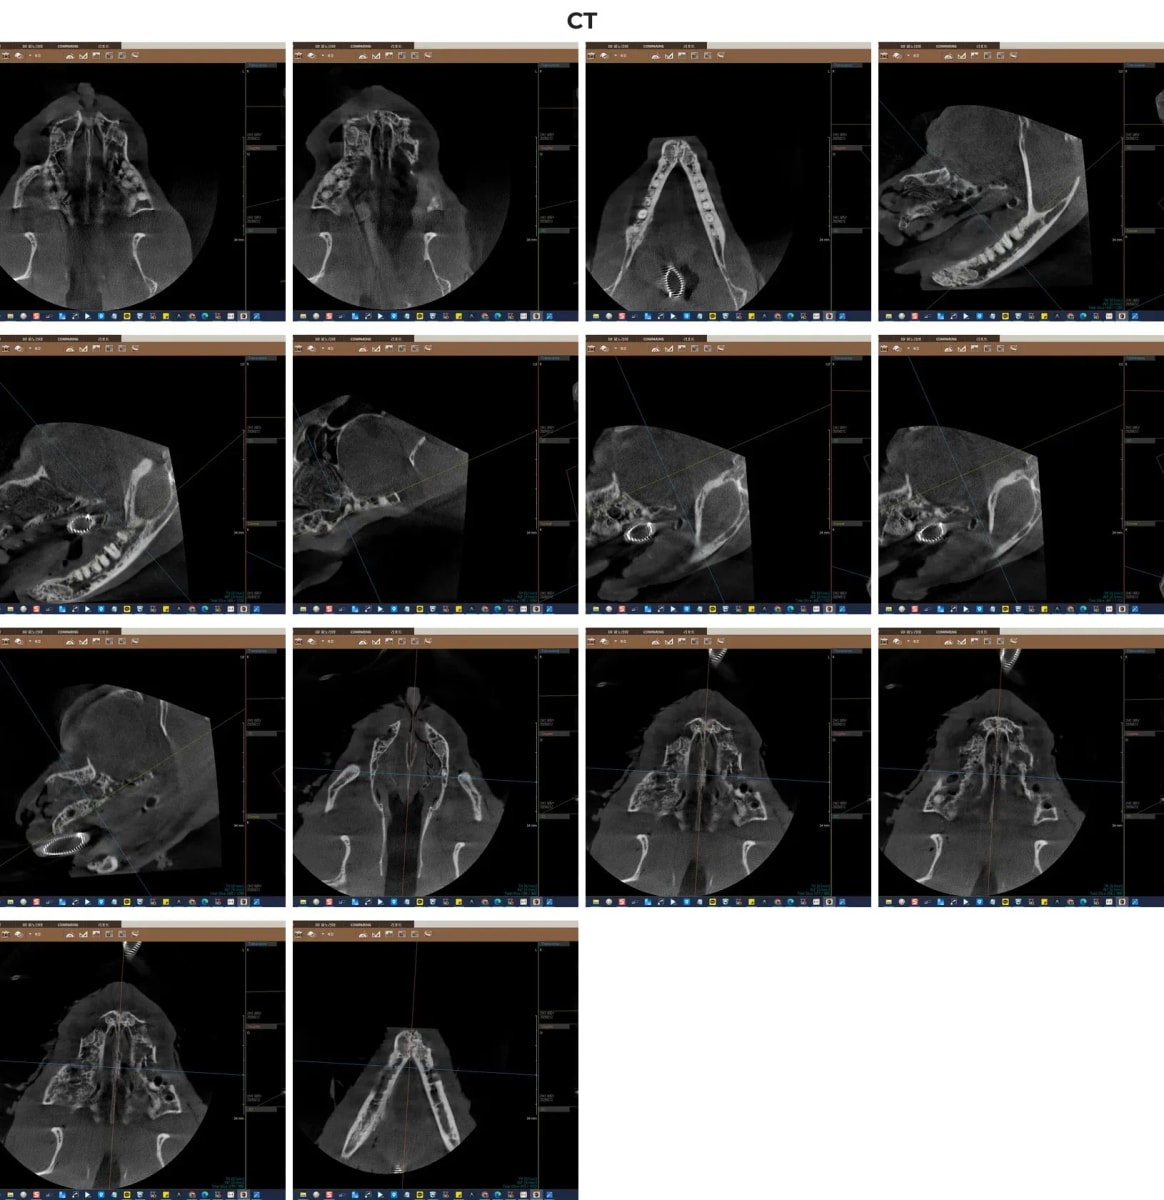

신체검사 시 육안상으로는 치아가 보이지 않았지만, 잇몸의 극심한 부종과 염증 반응은 심상치 않았습니다. 정확한 원인 파악을 위해 일반 두부 방사선을 촬영해 본 결과, 충격적이게도 다수의 치아 뿌리(잔존 치근)가 잇몸뼈 속에 그대로 남아있는 것으로 강하게 의심되었습니다.

정확한 재수술 계획을 수립하기 위해서는 남은 뿌리의 정확한 3차원적 위치와 주변 치조골(잇몸뼈)의 손상 정도를 완벽히 파악해야 합니다.

ℹ️ 치과 CT의 중요성

잔존 치근은 이미 잇몸이 덮여 있고 턱뼈 깊숙이 숨어 있어 일반 엑스레이만으로는 그 깊이와 뼈의 유착 정도를 100% 파악하기 어렵습니다. 광주 치과 동물병원 중 유일하게 본원이 보유한 수의 치과 전용 CT를 활용하면, 남은 치근 조각의 정확한 크기, 위치, 그리고 하악 신경관과의 거리를 밀리미터 단위로 분석하여 턱뼈 골절 위험 없이 안전한 재수술이 가능합니다.

치과 CT를 통해 잇몸뼈 속에 숨겨진 잔존 치근의 3차원적 위치를 파악하는 영상 소견